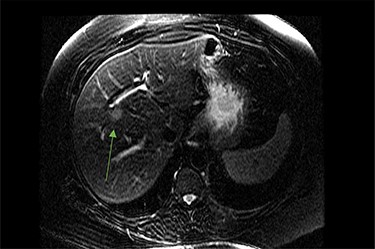

On assessment, the patient denied any symptoms related to her neuroendocrine tumor, including flushing, increased sweating, increased heart rate, wheezing, shortness of breath, diarrhea, weight loss or appetite changes. The only significant family history was a paternal and maternal grandfather with colon cancer. Imaging results were significant for computed tomography (CT) of chest demonstrating very small, but multiple, pulmonary nodules. A CT abdomen and pelvis demonstrated the known neuroendocrine tumor near the ileocecal valve (Fig. 1) as well as two poorly visualized liver lesions (Figs 2–4). The magnetic resonance imaging (MRI) demonstrated two separate one-centimeter lesions in segment 5 and 7 of the liver (Figs 5 and 6). The portal vein lacked normal left and right bifurcation; there was a circumferential right portal vein, which coursed anteriorly and superiorly and ultimately to the left lobe of the liver.

MRI image again demonstrating segment 5 metastatic lesion in close proximity to portal vein.